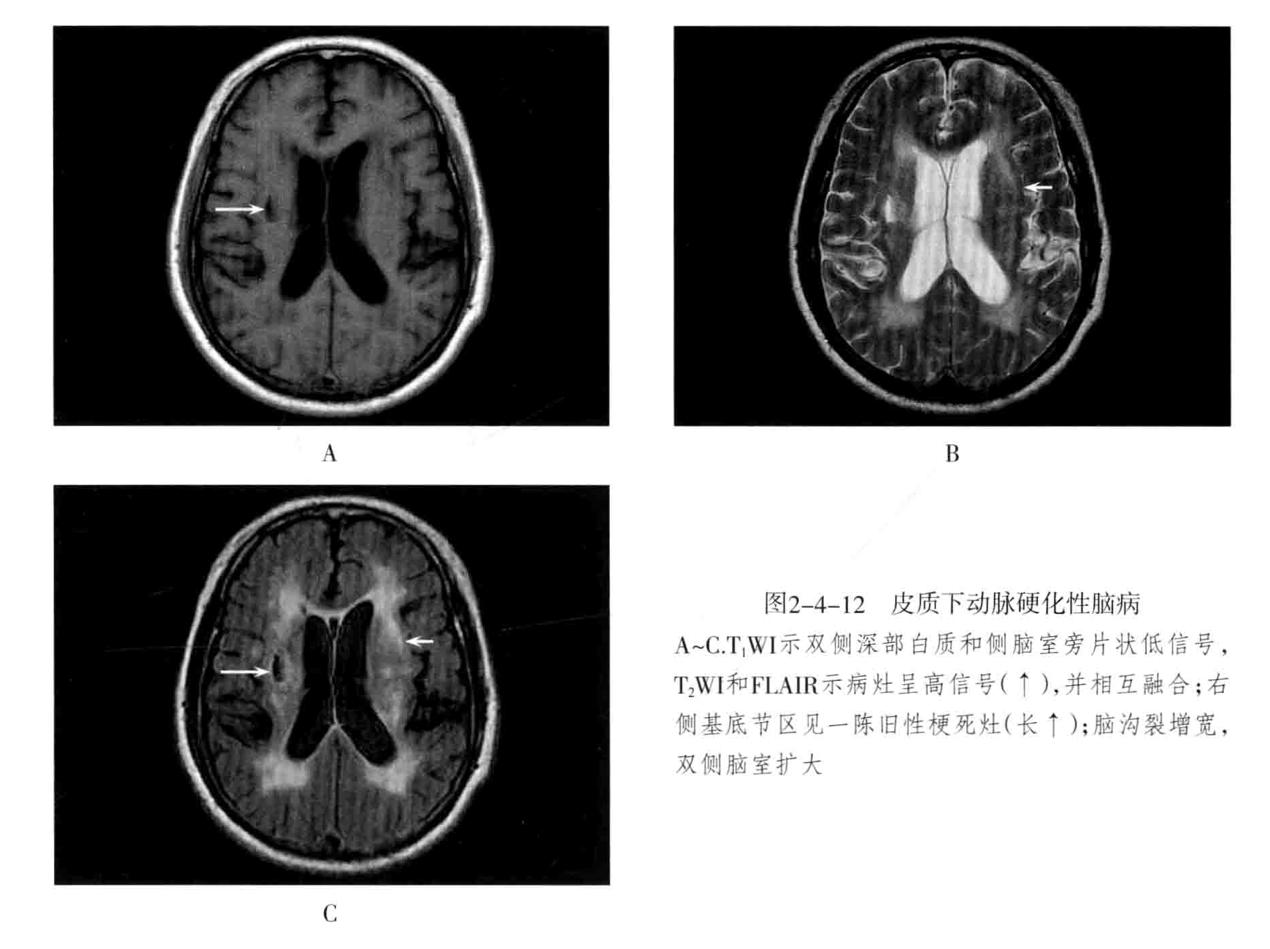

九、皮层下动脉硬化性疾病

又称为Binswanger病、进行性皮质下血管性脑病。为老年人在脑动脉硬化基础上的大脑半球白质弥漫性脱髓鞘性脑病。大多数发生在50岁以上。主要累及侧脑室周围、半卵圆中心等皮质下脑深部白质,多为双侧性,常伴有腔隙性脑梗死、脑萎缩。临床表现为进行性痴呆。病情可缓解,并反复加重。

1. CT平扫表现为侧脑室周围及半卵圆中心脑白质可见斑片状低密度影,以侧脑室前角、后角周围最为明显,严重者大脑各叶白质全部明显累及,双侧对称性分布。可伴有不同程度脑萎缩,常合并基底节区、丘脑区多发性腔隙性梗死灶。

2. MRI表现为中央半卵圆区及双侧侧脑室旁,尤以前角附近明显,侧脑室周围病灶常融合成不规则带状,且双侧比较对称。T1WI低信号,T2WI高信号,无占位效应。